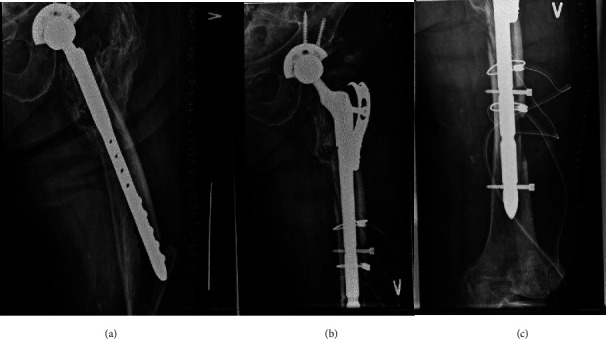

Background and Purpose: Revision total hip arthroplasty (rTHA) is a challenging procedure especially in the presence of severe bone loss where implant fixation is compromised. The aim of this study was to evaluate implant survival, clinical outcome, and midterm results in a group of complex patients after femoral revision using an uncemented modular implant design. Patients and Methods: We performed a retrospective study including 100 patients (101 hips) treated with revision THA using an uncemented modular implant design. We identified 51 hips as Paprosky types I-II and 50 hips as Paprosky III-IV bone defects. We reviewed operative reports and radiographs. Patients underwent a clinical examination to assess the Harris Hip Score (HHS) and completed patient-reported outcome measures (PROM), including the Oxford Hip Score (OHS) and the EQ-5D Visual Analog Scale (VAS). Minimum follow-up was 2 years (average, 5.8 years; range, 2.0-9.4 years). Results: Among the cases, 46 hips were revised for infection in a 2-stage procedure and 44 hips for aseptic loosening. 11 hips had periprosthetic fractures of Vancouver type B2 or B3. A total of 5 hips required revision with removal of the femoral implant and 11 patients experienced complications resulting in fracture (n = 1), dislocation (n = 10), and soft tissue revision (n = 1). The 5-year implant survival estimated by Kaplan-Meier survival analysis was 95% (95%-CI: 91%-99%). All hips had radiographic evidence of osseointegration and no one with subsidence greater than 5 mm. Additionally, 80% showed radiographic evidence of restoration of proximal femoral bone. Mean HHS was 78. Conclusion: In complex cases of revision THA, using a modular revision femoral system yielded promising results. The 5-year implant survival estimated by Kaplan-Meier survival analysis was 95% (95%-CI: 91%-99%), with all hips demonstrating radiographic evidence of osseointegration and no one with subsidence greater than 5 mm. Notably 80% showed radiographic evidence of restoration of proximal femoral bone.